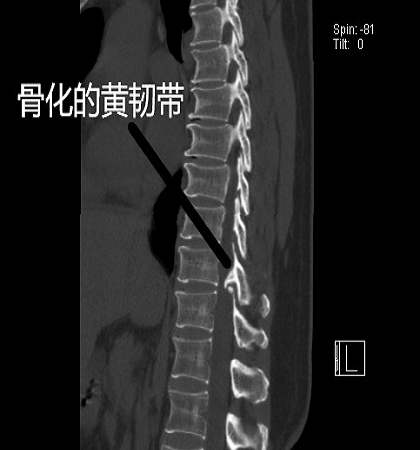

朱亮博士通过了解患者的病情,并且仔细的查体,发现患者的双下肢力量减退明显,并且膝腱反射呈亢进的状态,他认为患者目前的病情与腰椎间盘突出症不相符合,于是给予患者进一步的检查。通过核磁共振以及CT发现,患者胸椎T10/11水平黄韧带骨化,对脊髓造成了明显的压迫,是导致向女士目前症状的主要原因。

手术前的影像学检查